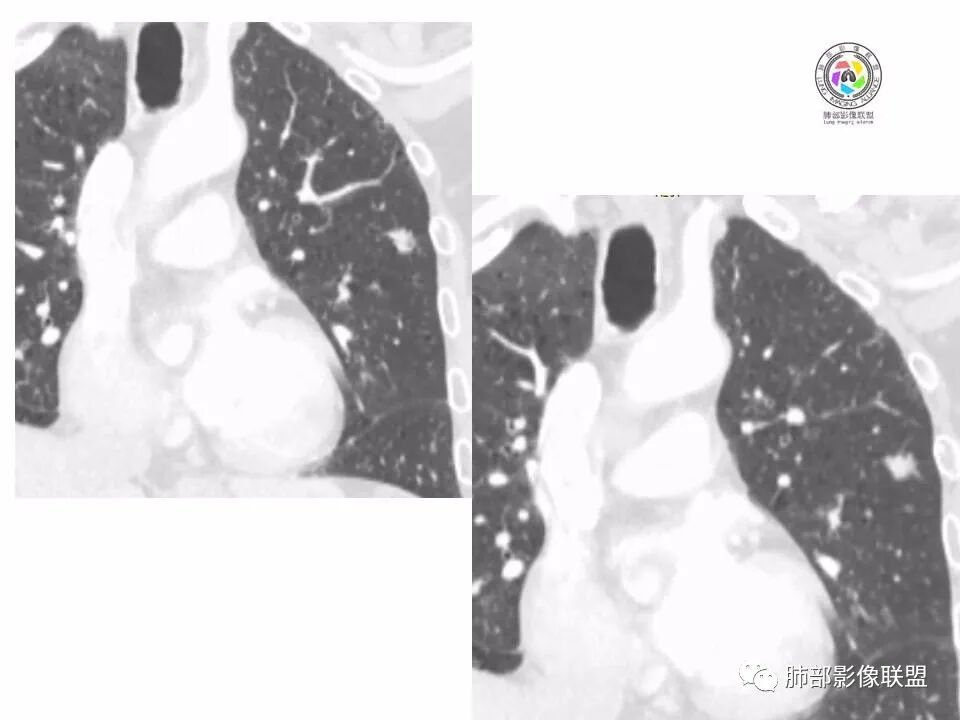

左肺上叶小结节,边缘毛糙,血管集束,支气管截断,强化较明显,但U型凹陷,部分边缘平直,总体感觉恶性大于良性,首选腺癌,鉴别炎性肉芽肿。

左上肺结节,月牙征,边缘纠集有收缩力,小空泡,血管增粗进入,纵隔淋巴结增大,考虑恶性,隐球菌待排。

老年男性,左上肺结节,边缘毛糙,临近血管进入增粗,内部隐约可见小空泡或远端扩张支气管,血管集束并伴月牙铲,有个横断界面看似像脐凹征,常规考虑腺癌,鉴别隐球。

结节,分叶,边缘毛糙,小空泡,血管集束并伴月牙铲,有强化,老年男性,考虑腺癌,建议复查除外结核。

左肺上叶混合密度结节,边缘见边缘清楚磨玻璃,分叶,U型凹陷,首先考虑腺癌。

左肺上叶结节影,边缘可见分叶,血管集束及月牙铲征,病灶内见小空泡影,考虑腺癌可能。

结节密度不均匀,混合磨玻璃结节,大部分实性部分,边缘清,月牙铲征,肿瘤微血管征,考虑肺癌。

老年男性,体检发现左肺上叶结节,周围浅分叶伴磨玻璃影,有血管相连,U型凹陷,纵隔见肿大淋巴结,考虑为恶性,腺癌可能。

左肺形态不规则结节,边缘收缩,毛刺,有月牙铲,纵隔窗比肺窗小,不密实,近段血管与病灶相连,强化不明显,老年男性,综合考虑,恶性,腺癌,鉴别炎性结节。建议穿刺。

老年男性,左肺上叶结节,边界清,不规则,有毛刺,血管集束,空泡,边缘有气肿带,考虑腺癌,鉴别肉芽肿。

左肺上叶小结节,边缘毛糙,血管集束,支气管截断,有月牙铲,首选腺癌,鉴别炎性肉芽肿。

左上肺实性小结节,短毛刺,月牙铲,似见小空泡,血管集束,有轻度强化,首先考虑腺癌。

老年男性,肺气肿背景,左肺上叶小结节,大部分边缘平直,部分边缘膨隆,局部可见月牙铲,边缘少许磨玻璃,边界清晰,血管进入,轻度强化,首先考虑腺癌,常规抗炎后复查,除外炎性结节。

左上肺结节,短毛刺,空泡,月牙铲,脐凹征,考虑腺癌。

左肺上叶混合密度结节,边界清,分叶,毛刺,血管进入,月牙铲,有强化,首先考虑腺癌,有平直边,收缩力不明显,常规先抗炎。

左上肺结节分叶,边缘毛糙,小空泡可能,血管集束,月牙,纵隔窗面积小于肺窗,有磨玻璃成份,有强化,老年男性,白细胞高,恶性的征象都有,但磨玻璃的形态和边界不好评估,实性为主,看形态和边缘局部较散缺乏饱满感,顶着压力反着来猜炎性可能大。复查不消失会考虑腺癌或黏液腺癌。

老年男性,肺气肿背景,左肺上叶实性结节,边界清,边缘平直为主,细长毛刺,较明显强化,考虑炎性病灶,隐球?

老年男性,左肺上叶结节,边缘可见长毛刺、较软,并可见分叶,周围可见清楚磨玻璃密度,内可见空泡征,增强后呈均匀强化,良恶性征象都有,感觉收缩力不强,化验白细胞偏高,建议抗炎治疗后复查除外腺癌。

老年男性,左肺上叶混合密度结节,空泡,分叶,血管集束,有强化,考虑腺癌;细长软毛刺,血管走行自然,边缘有平直收缩,白细胞高,肿标正常,考虑炎性结节。猜炎性结节,鉴别腺癌。

左肺上叶前段mGGN,边缘见毛刺及月牙铲,考虑腺癌,需要薄层图像确认所见征象。

左肺上叶结节,分叶,边缘毛糙,小空泡,月牙铲,有强化,考虑浸润性腺癌,鉴别炎性肉芽肿。

患者老年男性,体检发现。查癌胚抗原不高。血常规血象升高。胸部CT:肺气肿背景,左肺上叶近胸膜下实性结节,边缘光滑,边界清楚,可见毛刺、血管集束、月牙铲征象,增强不明显,内可见低密度区,综合考虑恶性病变,腺癌可能大,鉴别结核及炎性结节。

老年男性,左肺上叶结节,周围浅分叶伴磨玻璃影,有血管相连,月牙铲。纵隔见肿大淋巴结,但白细胞高。腺癌首先,需排除炎性假瘤。抗炎治疗后复查。

老年男性,体检发现左肺结节,分叶、脐凹、月牙铲及月牙铲附近有边缘清楚的磨玻璃影,上述征像均指向恶性肿瘤,有疑问的地方:毛刺软无力,无胸膜牵拉及白细胞计数升高。整体是腺癌,需要抗议后复查以排除炎性病变。

图片有限,左肺上叶结节病灶,有张力,有收缩及小泡征,边缘可见月牙征,周围长毛刺及血管集束征,增强目测有中度以上强化,首先考虑恶性病变,腺癌。

左肺上叶前段小结节,边缘稍毛糙,月牙铲,血管进入可疑脐凹征,小空泡?增强有强化,老年男性,要高度警惕腺癌,但感觉毛刺偏细软,周围磨玻璃不明显,常规查隐球菌荚膜抗原除外隐球菌,血象高,抗炎后短期复查除外炎性结节。

左肺上叶mGGN,边缘收缩平直为主,肺窗显示清楚,纵隔窗体积缩小,未见胸膜牵拉,倾向感染性结节,隔期复查。